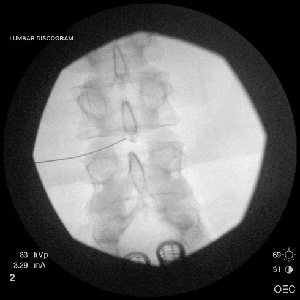

Provocative Discography

It is a diagnostic test to assess if small tears within the disc that can cause discogenic back pain. Contrast dye is injected into the disc nucleus(the gel-like substance in the center of the disc). This is the only diagnostic test that provides both anatomical and functional information about a diseased disc causing discogenic pain, and can identify problems that may not be seen on MRI or CT. Discography is also helpful in specifically localizing the disc level that needs to be treated.

Under fluoroscopic (X-ray) guidance, Dr. Barr will insert a needle into the disc. Contrast dye is injected and an X-ray (discogram) is taken, which may show tears in the outer portion of the disc (annulus).

During the disc injection portion of the procedure, the patient will be asked if the increased pressure in the disc causes discomfort. Specifically, the patient will be asked to describe any discomfort with particular attention to the reproduction of the patient’s “typical back pain” in quality and location. Those disc injections which reproduce the patient’s “typical back pain” and have evidence of tears within the annulus (outer portion of the disc) are considered positive and likely are the etiology of the patient’s back pain.